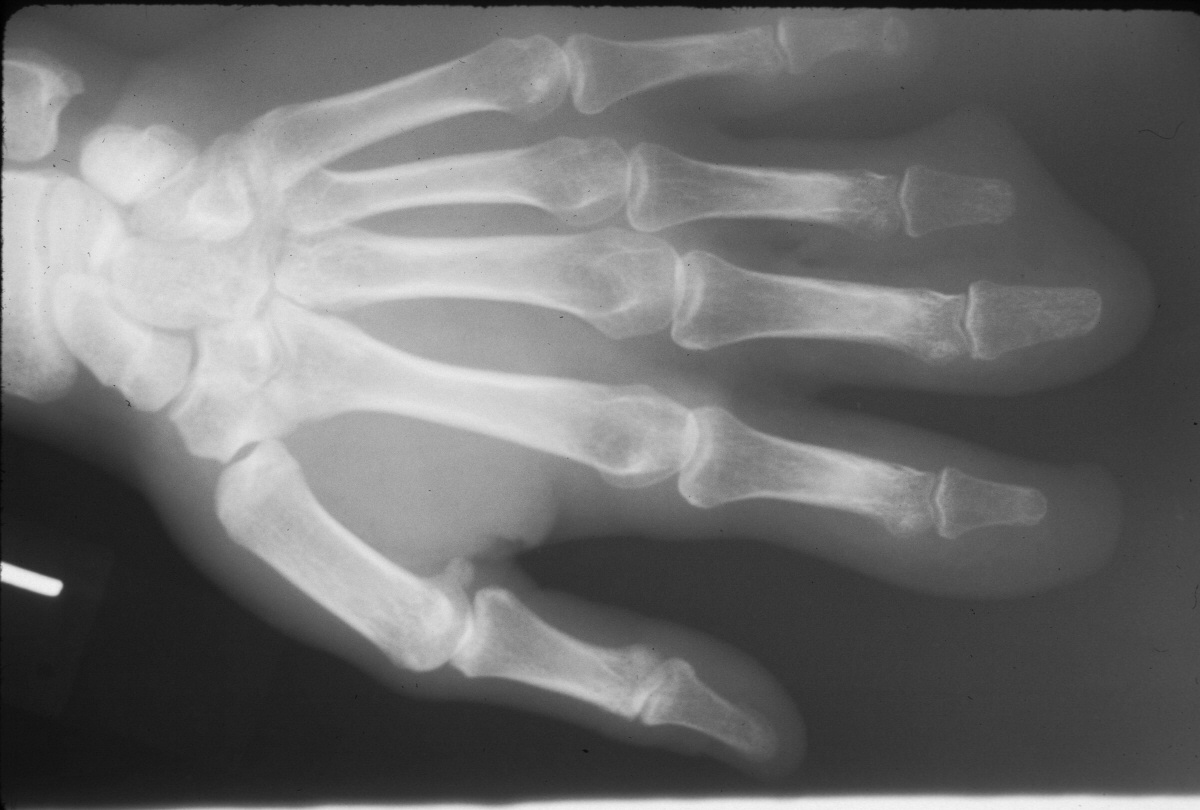

Clinical Example: Multiple finger degloving treated with medial cross arm flap and temporary syndactyly

Degloving injuries are commonly the result of industrial injuries involving high speed rollers or presses. Reconstruction is difficult because of the complexity of soft tissue loss. Skeletal elements maintain vascularity only to the most proximal phalanx distal to the most proximally degloved joint, and more distal phalanges should be discarded. This case demonstrates the first stages of reconstruction of a degloving injury of all fingers using a medial cross arm flap and temporary syndactyly within the flap.

Initial injury: